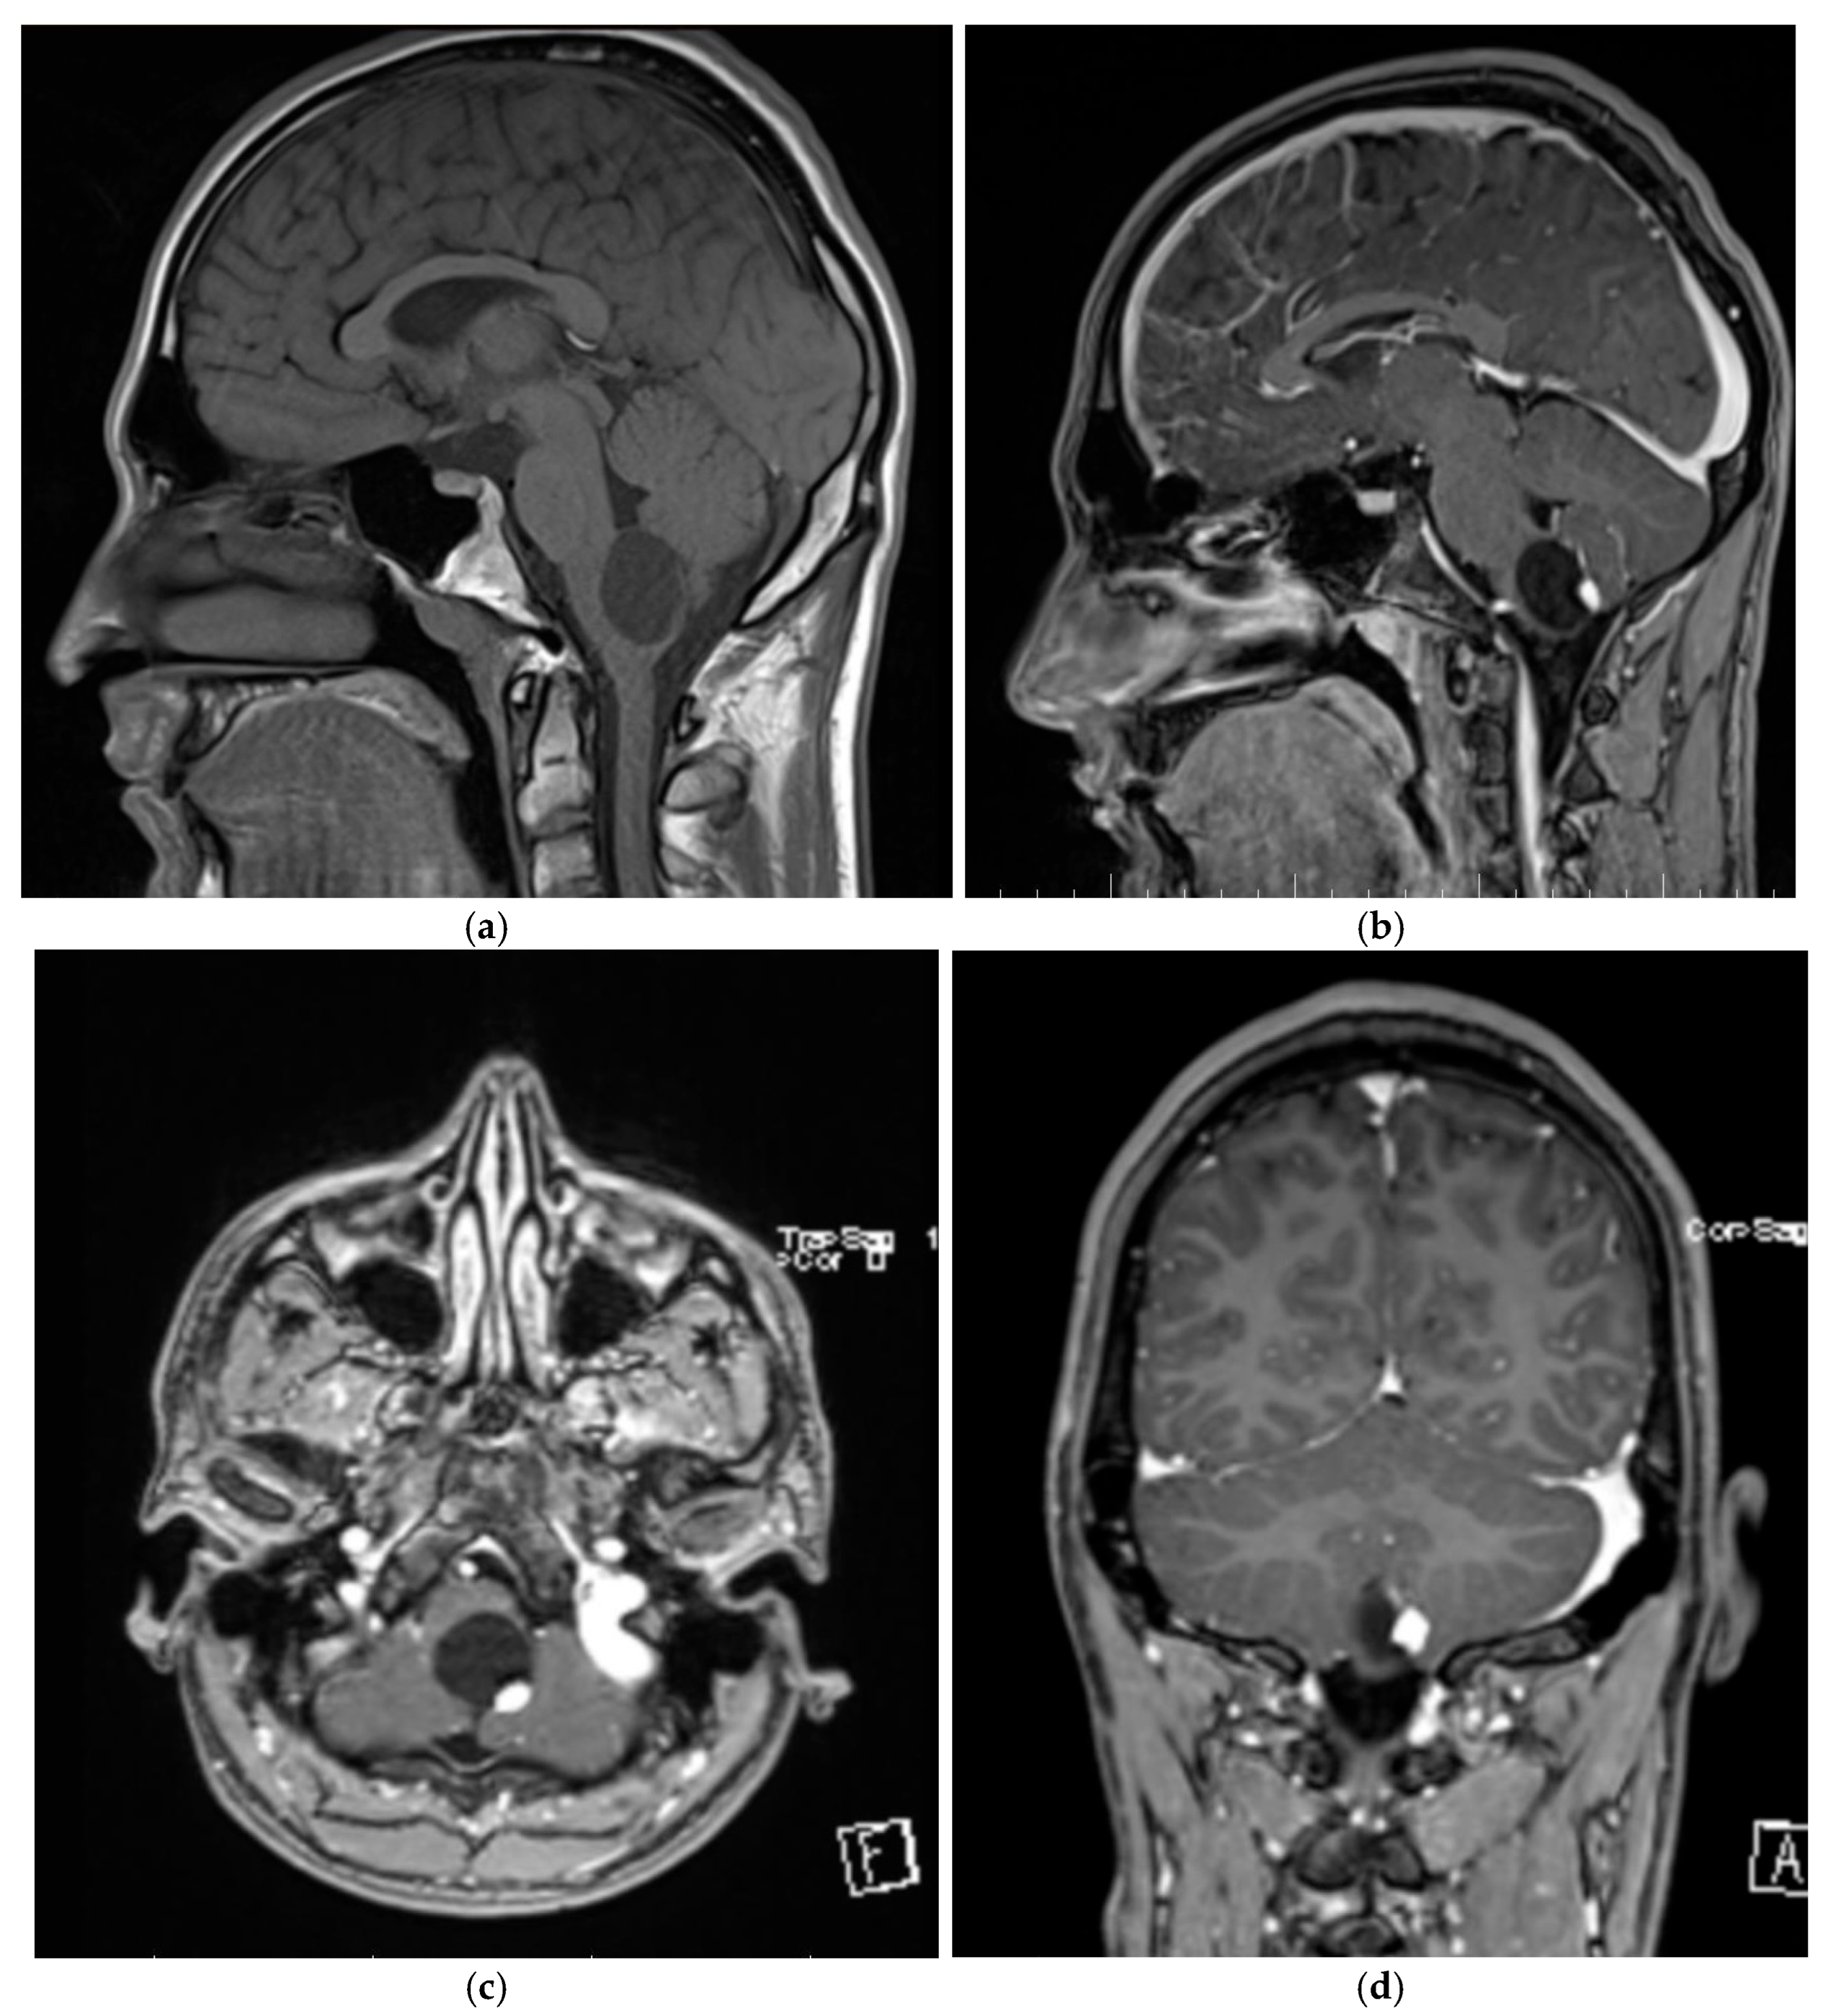

3.1.1. Patient One

3.1.2. Patient Two

3.1.3. Patient Three